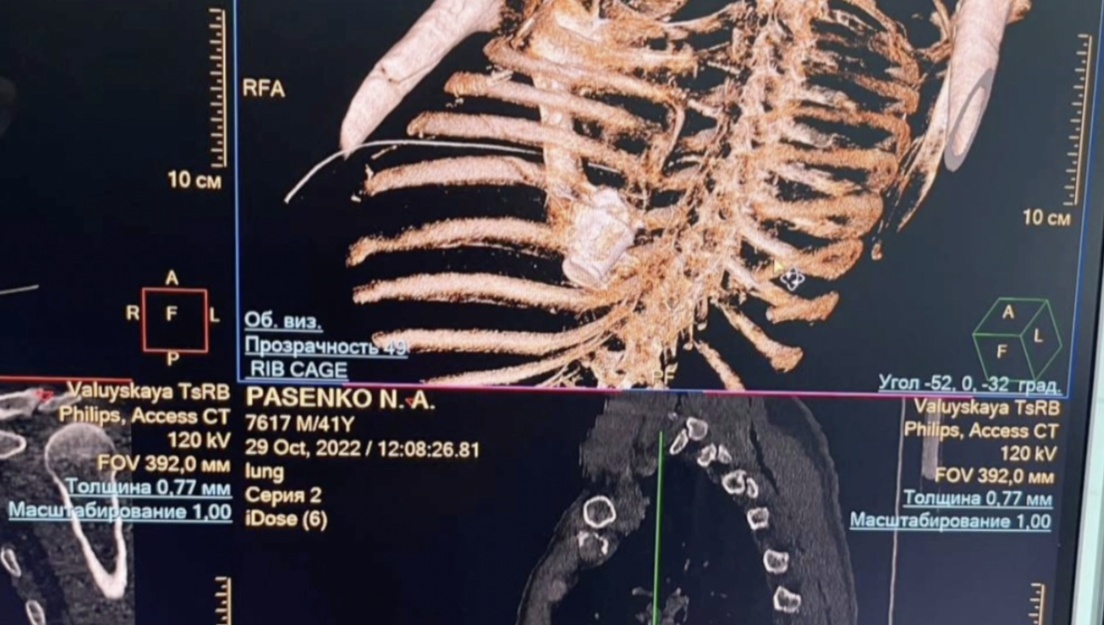

La munición, proveniente de las fuerzas ucranianas, perforó las costillas del sargento Nikolái Pasenko, los pulmones y se detuvo en la columna vertebral entre la aorta y la vena cava inferior, cerca del corazón.